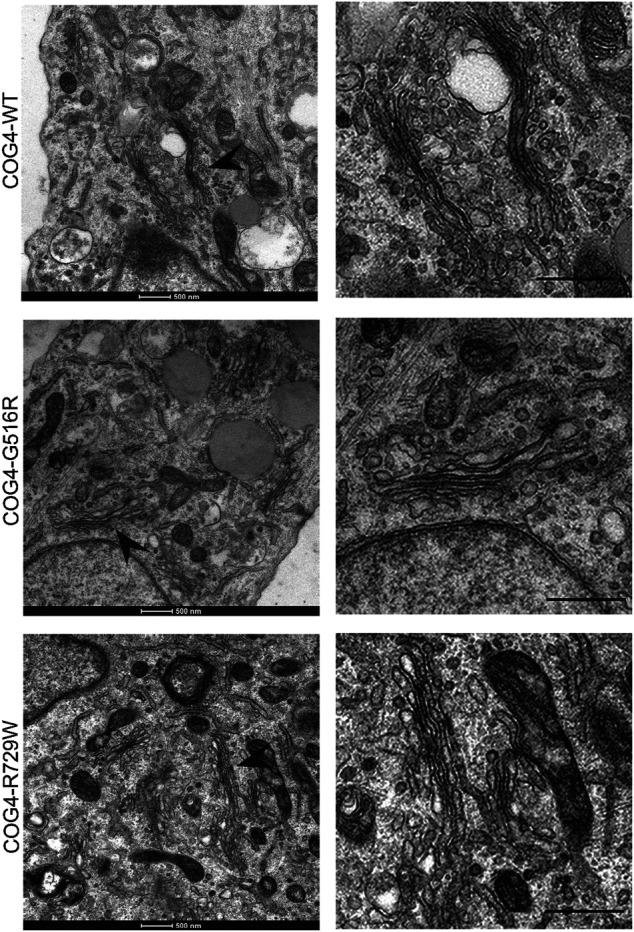

Conserved Oligomeric Golgi (COG) is an octameric protein complex that orchestrates intra-Golgi trafficking of glycosylation enzymes. Over a hundred individuals with 31 different COG mutations have been identified until now. The cellular phenotypes and clinical presentations of COG-CDGs are heterogeneous, and patients primarily represent neurological, skeletal, and hepatic abnormalities. The establishment of a cellular COG disease model will benefit the molecular study of the disease, explaining the detailed sequence of the interplay between the COG complex and the trafficking machinery. Moreover, patient fibroblasts are not a good representative of all the organ systems and cell types that are affected by COG mutations. We developed and characterized cellular models for human COG4 mutations, specifically in RPE1 and HEK293T cell lines. Using a combination of CRISPR/Cas9 and lentiviral transduction technologies, both myc-tagged wild-type and mutant (G516R and R729W) COG4 proteins were expressed under the endogenous COG4 promoter. Constructed isogenic cell lines were comprehensively characterized using biochemical, microscopy (superresolution and electron), and proteomics approaches. The analysis revealed similar stability and localization of COG complex subunits, wild-type cell growth, and normal Golgi morphology in all three cell lines. Importantly, COG4-G516R cells demonstrated increased HPA-647 binding to the plasma membrane glycoconjugates, while COG4-R729W cells revealed high GNL-647 binding, indicating specific defects in O- and N-glycosylation. Both mutant cell lines express an elevated level of heparin sulfate proteoglycans. Moreover, a quantitative mass-spectrometry analysis of proteins secreted by COG-deficient cell lines revealed abnormal secretion of SIL1 and ERGIC-53 proteins by COG4-G516R cells. Interestingly, the clinical phenotype of patients with congenital mutations in the SIL1 gene (Marinesco-Sjogren syndrome) overlaps with the phenotype of COG4-G516R patients (Saul-Wilson syndrome). Our work is the first compressive study involving the creation of different COG mutations in different cell lines other than the patient's fibroblast. It may help to address the underlying cause of the phenotypic defects leading to the discovery of a proper treatment guideline for COG-CDGs.

保守寡聚高尔基体(COG)是一种八聚体蛋白复合物,负责协调高尔基体内部糖基化酶的运输。到目前为止,已经鉴定出一百多名携带31种不同COG突变的个体。COG先天性糖基化障碍(COG-CDGs)的细胞表型和临床表现具有异质性,患者主要表现为神经、骨骼和肝脏异常。建立细胞COG疾病模型将有助于该疾病的分子研究,解释COG复合物与运输机制之间相互作用的详细过程。此外,患者的成纤维细胞并不能很好地代表所有受COG突变影响的器官系统和细胞类型。我们开发并鉴定了人类COG4突变的细胞模型,特别是在RPE1和HEK293T细胞系中。使用CRISPR/Cas9和慢病毒转导技术相结合的方法,在COG4内源性启动子的作用下,表达了带有myc标签的野生型和突变型(G516R和R729W)COG4蛋白。使用生化、显微镜(超分辨率和电子显微镜)和蛋白质组学方法对构建的同基因细胞系进行了全面表征。分析显示,在所有三种细胞系中,COG复合物亚基的稳定性和定位相似,细胞生长正常,高尔基体形态正常。重要的是,COG4-G516R细胞显示HPA-647与质膜糖缀合物的结合增加,而COG4-R729W细胞显示GNL-647结合增加,表明O-连接和N-连接糖基化存在特定缺陷。两种突变细胞系中硫酸乙酰肝素蛋白聚糖的表达水平均升高。此外,对COG缺陷细胞系分泌的蛋白质进行定量质谱分析发现,COG4-G516R细胞异常分泌SIL1和ERGIC-53蛋白。有趣的是,SIL1基因先天性突变患者(马里内斯科-舍格伦综合征)的临床表型与COG4-G516R患者(索尔-威尔逊综合征)的表型重叠。我们的工作是首次在患者成纤维细胞以外的不同细胞系中创建不同COG突变的综合研究。它可能有助于找出表型缺陷的根本原因,从而发现针对COG-CDGs的合适治疗指南。